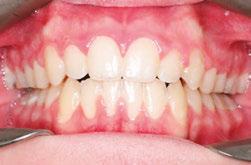

A 40-year-old patient’s concern was crowded incisors following a relapse of treatment completed as a child. The clinical exam showed a constricted/omega-shaped maxillary arch with retroclined central incisors and moderate crowding of the mandibular incisors with a severe Curve of Spee and corresponding deep bite.

Deep bite cases are some of the more challenging ones to treat with clear aligners.

I began, as I always do, with the development/expansion of the maxillary arch and simultaneous uprighting of the mandibular posterior teeth. Expansion creates a reciprocal movement of retraction/retroclination for incisors, so it was necessary to counter this effect by inducing constricting force on the patient’s second molars during case setup (this is often favorable since second molar teeth tend to be overexpanded naturally due to minimal muscle tone buccal to this region). Constriction of second molars coincides with premolar expansion and proclination of both upper and lower incisors during the first phase of tooth movement, during which alignment is mostly achieved. This is

Figure 6: Case 1 initial photos

Figure 7: Case 1 initial (left) and final (right) photos showing correction of retroclined incisors

Figure 8: Case 1 final photos

followed by intrusion and retraction of the lower incisors with lingual root torque during the second phase.

The patient received 25 aligners initially and was able to wear them to completion with no tracking issues. At a pace of one aligner per week, the patient returned for a refinement at the 25-week mark with a near-perfect alignment but with minor loose contacts. I also felt he could benefit from additional arch development/expansion, so I programmed this into his following setup, which came to 13 stages. Unfortunately, due to a mix-up on our end, his case did not get submitted right away, meaning we would not get his aligners back in time for his appointment. To resolve this, we exported the first three upper and lower .stl files from his setup (a nice feature of the Spark system) and printed the models in-house so treatment wouldn’t be delayed. Once the remaining aligners were received from Spark, he picked them up from our front desk and proceeded with trays 4-13, after which his treatment was deemed complete. Total time was 15 months from scan to retainer.